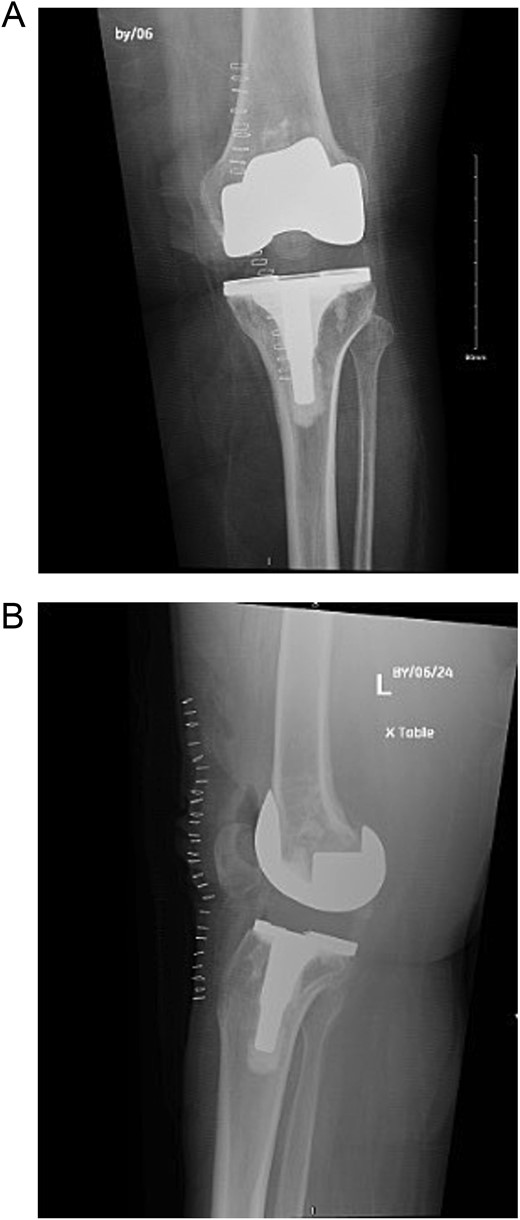

The case involves a 48-year-old obese woman with a body mass index (BMI) of 42, a known medical history of polio, and a baseline of bilateral knee hyperextension of 5º, who underwent bilateral staged TKA with posterior stabilized knee prosthesis in 2018 with a good functional level and outcome (Fig. 1).

Anteroposterior view of both knees post bilateral staged total knee arthroplasty.